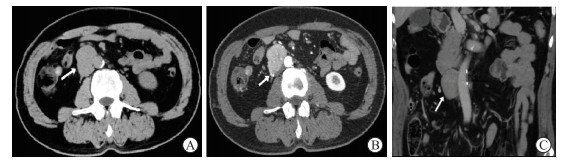

图  1  1例40岁女性腹部单中心型Castleman病患者的影像学表现(体检发现腹膜后占位)

A:CT平扫示腹主动脉左侧见椭圆形实性肿块,密度均匀(CT值为39.6 HU);B:CT增强动脉期示肿块明显强化(CT值为120.0 HU),中央可见裂隙状低密度影(箭头所示),瘤周见血管影;C:CT增强延迟期示肿块强化均匀(CT值为92.8 HU),呈速升缓降强化模式. CT:计算机断层扫描.

• 图  1   1例40岁女性腹部单中心型Castleman病患者的影像学表现(体检发现腹膜后占位)